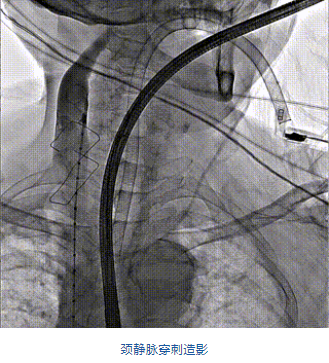

團隊前期經(jīng)過多次討論,制定了周密的手術(shù)策略和預(yù)案。由于患者已是近九旬的超高齡老人,傳統(tǒng)外科開胸手術(shù)風險極高,純介入經(jīng)血管三尖瓣替換能夠明顯減少創(chuàng)傷。術(shù)中陳茂及馮沅教授結(jié)合體表定位在造影指示下精準穿刺右側(cè)頸靜脈并預(yù)置兩把血管縫合器。成功建立經(jīng)皮血管入路后在食道超聲和DSA的引導(dǎo)下順利完成人工瓣膜植入,術(shù)后超聲和造影顯示人工三尖瓣同軸性良好,瓣架固定牢靠,無反流和瓣周漏,平均跨瓣壓差降為1mmHg。術(shù)畢收緊預(yù)置的血管縫合器縫線完成止血,縫合效果滿意,在手術(shù)室即刻拔除氣管插管。